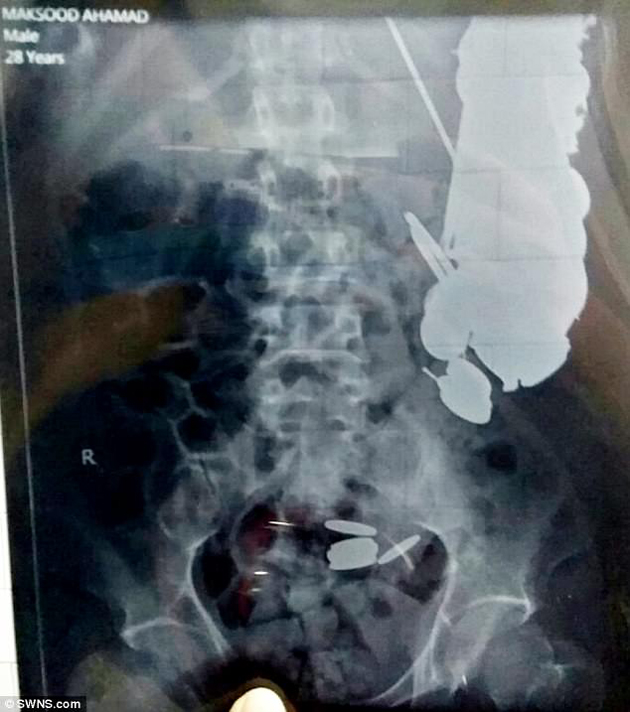

No menos de 263 monedas y 150 clavos tenía un sujeto que fue atendido por los cirujanos indios quienes trataron una presunta intoxicación alimentaria, quedando sin palabras cuando vieron el origen de su malestar.

Los objetos estaban alojados en el estómago e intestinos, según informa el periódico The Times of India, además se comió un trozo de correa de acero para perros, alfileres, una larga tira de metal, aguja de acolchar, metales puntiagudos y picos de hierro. La operación, realizada en el Hospital Sanjay Gandhi en la ciudad de Rewa (noreste del país), supuso la extracción de un poco más de 2 kilos de objetos del estómago del hombre.

El paciente de 32 años —a quien el periódico Daily Mail atribuye el nombre Maksud Khan— ingresó en el hospital con dolores abdominales. Se reporta que el hombre sufre problemas de salud mental. Sus familiares dicen que había entrado en una depresión y que es posible que a partir de ese momento empezara su adicción a comer objetos metálicos.